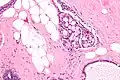

Collagenous spherulosis is characterized by a tubular/cribriform architecture with intratubular eosinophilic material that classically is arranged like the spokes of a wheel ("radial spikes"). There is usually no mitotic activity, and two cells populations (epithelial & myoepithelial) are present, like in benign breast glands.

The lesions are typically small (less than 50 spherules per lesion, less than 100 micrometers in size) and may be multifocal.

Intermed. mag. -